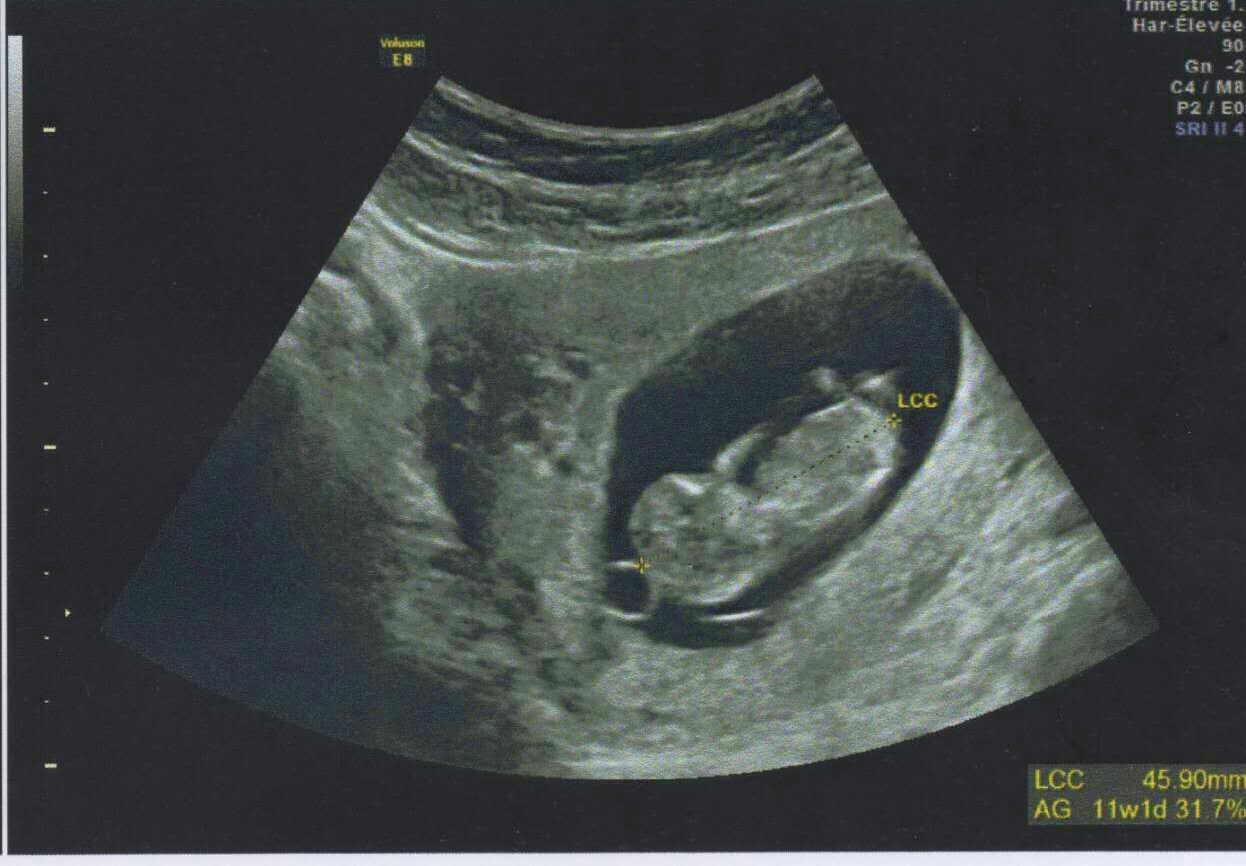

Posting for my sister whos 11weeks and 3days on this scan. Any guess? Attachment 30230